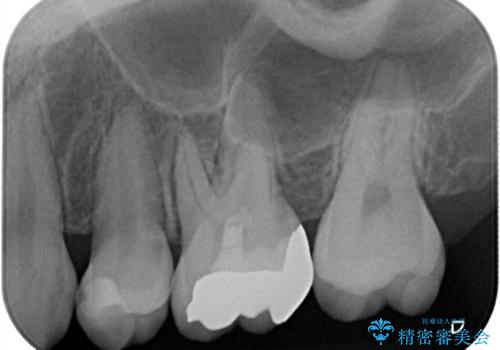

【VPT/歯髄温存療法・オールセラミッククラウン】虫歯が深く神経まで達していたが健康な神経は残す治療!

- 虫歯が神経まで達していたのですが、術前の検査と顕微鏡下で見た神経の状態からVPTの適応と判断し神経を残す治療をしました。

汚染されている神経は除去し残りの神経を残すためVPTを行いバイオセラミックのバイオシーシーラーで充填しオールセラミッククラウンで治療を行いました。治療後2年経過しましたが、神経は温存され経過は良好です。